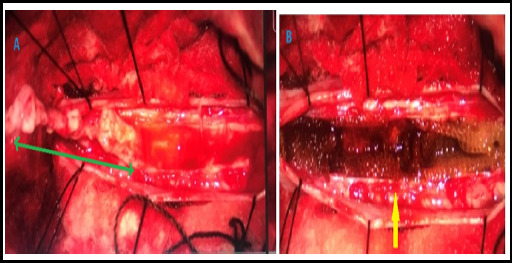

Spinal cord tumors, though uncommon, pose significant challenges due to their potential for neurological disability and mortality. Intramedullary spinal cord tumors, particularly Long-level intramedullary spinal cord tumors, present challenging clinical scenarios. Contrast-enhanced Magnetic resonance imaging remains pivotal for radiological evaluation and surgical planning. Notably, aggressive resection is advocated to enhance prognosis, with meticulous attention to preserving neurological function. Advancements in spinal surgery techniques, coupled with intraoperative monitoring, offer promising avenues for improved patient outcomes. We presented three cases of long-level intramedullary tumors, emphasizing the significance of tailored management and presented details, including clinical presentations, radiological findings, and histopathological results.

Abstract Image